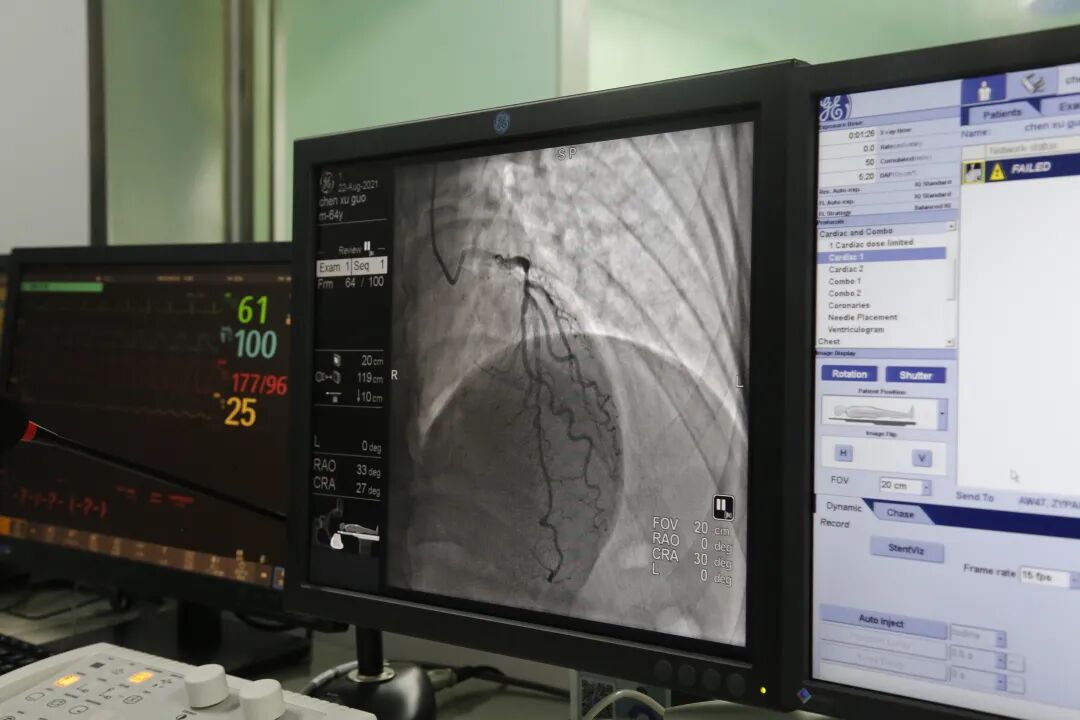

8月22日上午,在山东第一医科大学第一附属医院(山东省千佛山医院)心内科赵学强教授的指导下,在新泰市中医医院影像科董晓副主任、导管介入室李树娟副护士长等医护人员配合下,心血管病科房立文副主任、季仁波主治医师对局部浸润麻醉的上述患者实施DSA冠脉造影,结果显示:冠脉走行区均可见钙化影,左主干未见明显狭窄,前降支近中段可见60-70%狭窄,管壁钙化,TIMI血流3级。回旋支中段75%狭窄,TIMI血流3级,钝缘支开口90%狭窄,TIMI血流3级,管壁钙化。回旋支远段60%狭窄,TIMI血流3级。右冠近中段弥漫性钙化病变,狭窄50-60%,TIMI血流3级。

经与患者家属沟通,决定对病变明显的回旋支行PCI术,对其他病变血管暂时行内科药物保守治疗。术中应用导丝分别送至回旋支远端及钝缘支远端,应用球囊预扩张后造影显示病变血管狭窄改善不明显,遂给予支架一枚释放于回旋支中段至钝缘支开口,血管狭窄得到显著改善,手术顺利,病人术中无不适,拔除鞘管局部加压包扎,患者安返病房。